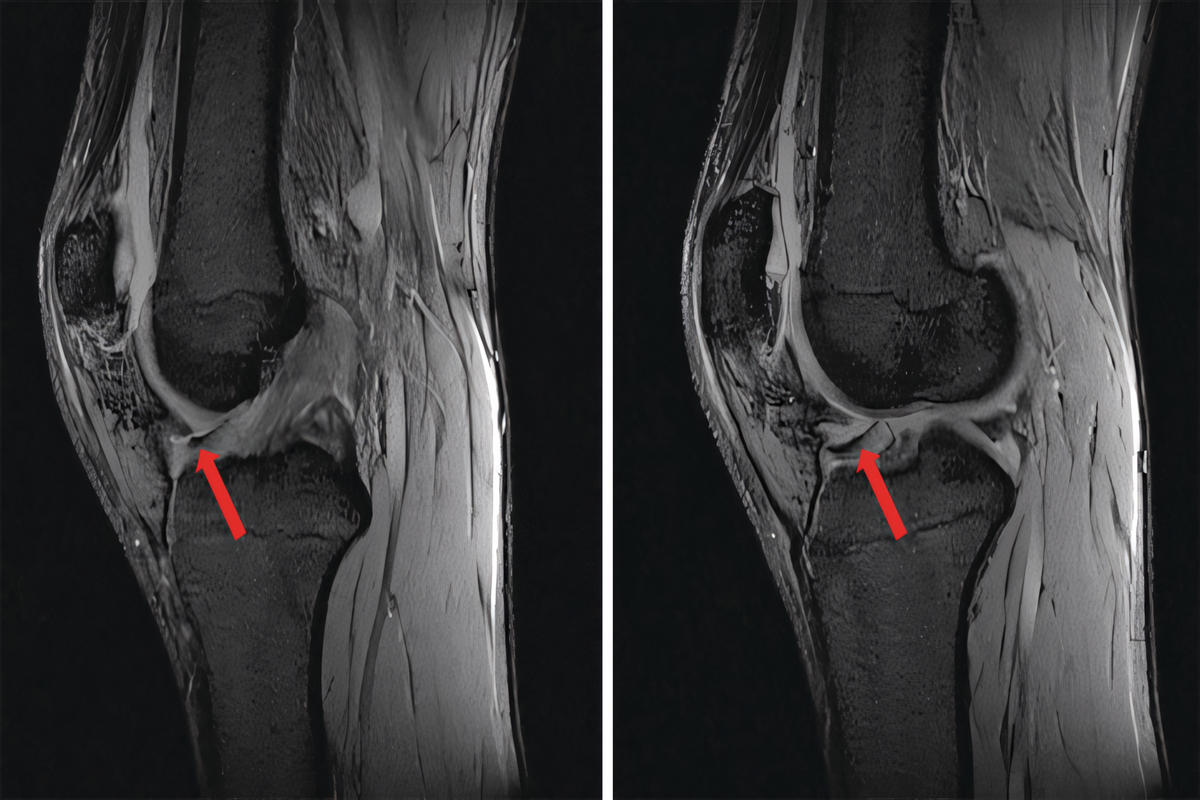

• Μαγνητική τομογραφία (MRI) για αποκλεισμό άλλων ενδαρθρικών παθήσεων

Η MRI δεν είναι πάντα διαγνωστική για το plica syndrome, αλλά βοηθά στον αποκλεισμό άλλων αιτιών πόνου στο γόνατο.

Η υμενική πτυχή αποτελεί εμβρυολογικό υπόλειμμα του αρθρικού υμένα. Υπάρχουν διάφοροι τύποι, με συχνότερη την έσω υμενική πτυχή (medial plica), η οποία λόγω της ανατομικής της θέσης μπορεί να τρίβεται στην έσω μηριαία τροχιλία ή στην επιγονατίδα.

Όταν η πτυχή παχυνθεί ή γίνει ινώδης, παύει να είναι ελαστική και αρχίζει να προκαλεί μηχανικό ερεθισμό κατά την κάμψη και έκταση του γόνατος.